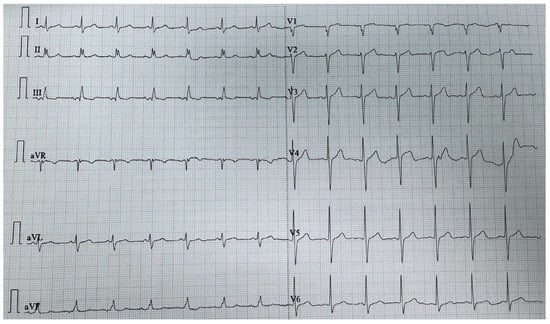

Swinging Mass Through the Pulmonary Valve: A Rare Case of Right Ventricular Myxoma

Primary cardiac tumors are rare, with an estimated incidence of 0.001% to 0.3% in autopsy series. Most are benign, the most common being cardiac myxomas, which typically originate in the left atrium. Right ventricular myxoma is among the rarest primary cardiac tumors, and its true incidence is difficult to determine, as most data come from isolated case reports. This paper aims to report a case of right ventricular myxoma in a young woman with a history of childhood malignancy and to discuss the possible association between the two conditions. Echocardiography, thoracic computed tomography (CT), and pulmonary CT angiography were used to assess the presence, location, and size of the tumor. The definitive diagnosis was established by histopathological examination. A 34-year-old woman, with a past medical history of acute lymphoblastic leukemia (ALL) in childhood, presented with a dry cough and exertional dyspnea persisting for three weeks. Transthoracic echocardiography revealed a mass located in the right ventricular outflow tract (RVOT), attached near the tricuspid valve and intermittently prolapsing into the pulmonary trunk. CT imaging confirmed the presence of the tumor in the RVOT and the main pulmonary artery. Because of the high risk of massive pulmonary embolism, the patient underwent urgent surgical excision of the tumor. Histopathological analysis confirmed the diagnosis of cardiac myxoma. The postoperative recovery was uneventful, and the three-month follow-up showed no recurrence or signs of pulmonary embolism. The patient’s history of ALL raised the question of a possible association; however, a review of the literature revealed no previously reported link. In conclusion, right ventricular myxomas are extremely rare. The occurrence of cardiac myxoma in this patient following childhood ALL appears to be incidental. Further research is needed to determine whether ALL survivors have an increased predisposition to subsequent cardiac tumors. Full article

Show Figures

Figure 1